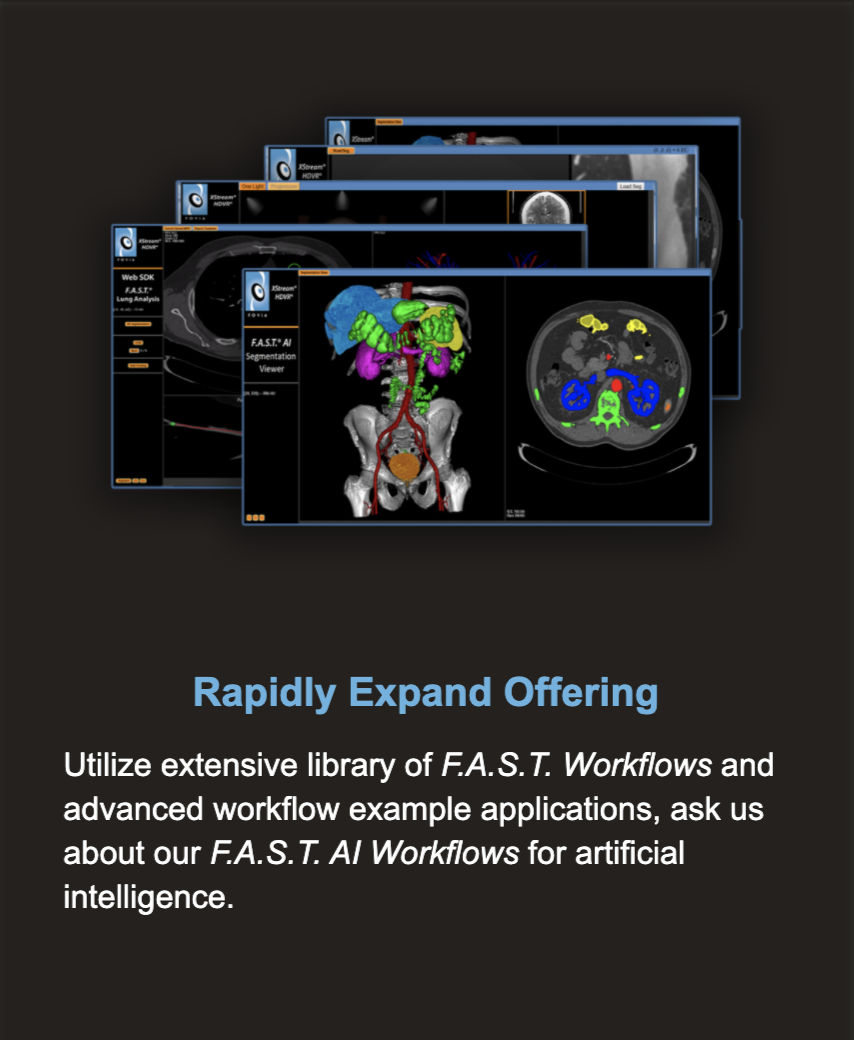

Representative F.A.S.T. Workflows

F.A.S.T. AI Workflows

Representative F.A.S.T. Workflows

F.A.S.T. AI Workflows